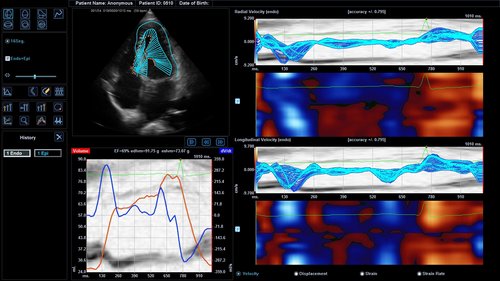

• M-Modus, Auto IMT, CV Measurement and Report, EKG, Cube Strain, Stressecho, Tissue Doppler Imaging (Kardiologie)